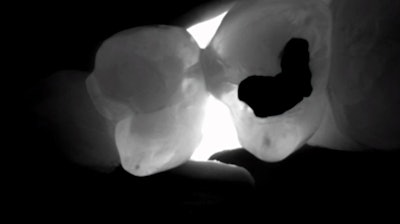

The transillumination mode, however, for me, was the game changer. The DiagnoCam’s special tip emits near-infrared light at the gingival level, from both the buccal and lingual aspects. The near-infrared light transmits through healthy enamel toward the camera, which has a corresponding bright, white appearance on the resulting image. Areas of carious or demineralized enamel scatter the light, resulting in a corresponding darker region.

Using the same radiograph from above (Figure 8), I transilluminated the questionable areas, yielding highly accurate discernment of the extent and location of various cavities.

Figure 9: This is the interproximal space between teeth #s12 and 13. Notice that, upon learning the location of these interproximal lesions, the practitioner doesn’t have to prepare the lingual extent of the interproximal box.Figure 9: This is the interproximal space between teeth #s12 and 13. Notice that, upon learning the location of these interproximal lesions, the practitioner doesn’t have to prepare the lingual extent of the interproximal box.

Figure 10: This is the interproximal space between teeth #20 and #21. Notice that both lesions are incipient and do not extend into the dentin. This provided further confirmation that a traditional class II prep would not be appropriate.Figure 10: This is the interproximal space between teeth #20 and #21. Notice that both lesions are incipient and do not extend into the dentin. This provided further confirmation that a traditional class II prep would not be appropriate.